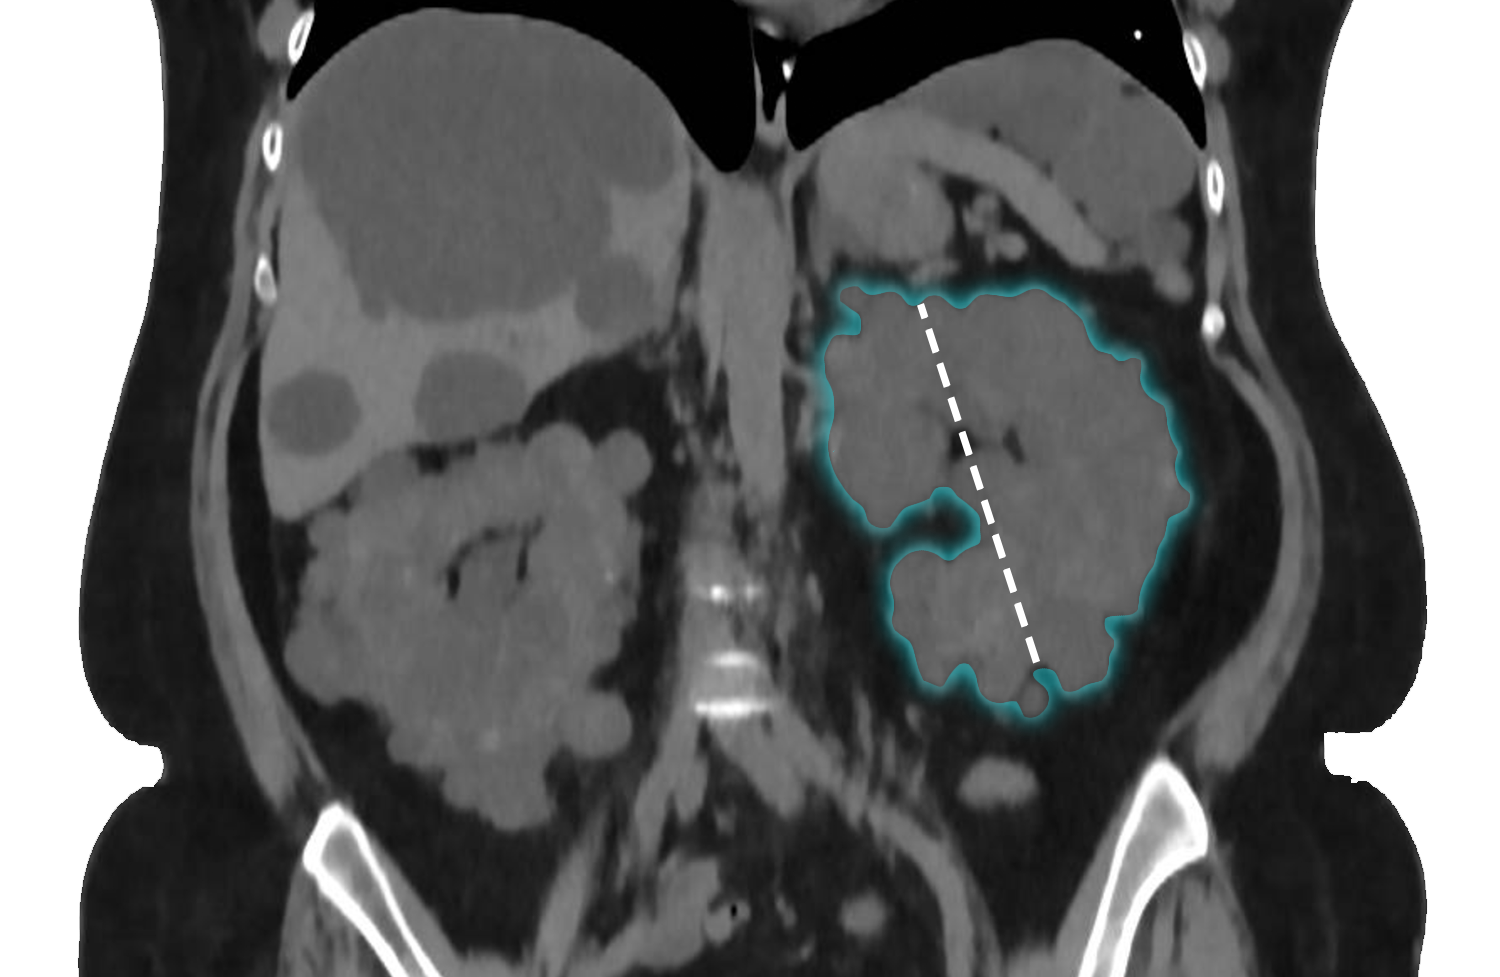

Kidney height

Measure the height along the coronal axis using a line parallel to the kidney's longitudinal axis at the point of greatest measurement. Ensure the line traces the edge of the renal parenchyma, excluding the outline of any protruding cysts